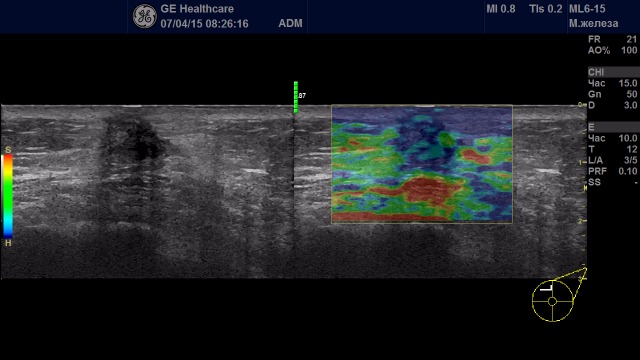

Образование с удовлетворительной эластичностью